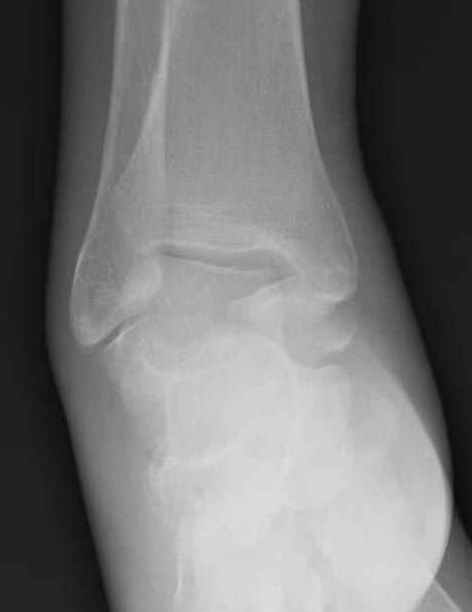

Уважаемые участники русского Ортофорума, поздравляю всех со всеми прошедшими праздниками: Новым годом, Рождеством, Hanukkah, Kwanzaa, желаю участникам всего наилучшего и здоровья.Повреждение таранной кости.Больной 81г автоавария, повреждение таранной кости, здесь снимки. Какие рекомендации?Djoldas Kuldjanov, MDDepartment of Orthopedic SurgerySt. Louis University Medical Center

Вдогонку по поводу перелома таранной кости, больная 81, не страдает диабетом, перелом закрытый, в первый же день поступления ограничились временным наружным фиксатором (как на снимке).

Планировалась открытая фиксация после спадения отека, но больная пожелала лечиться по месту жительству в другом штате..

За пару недель насчитал 5 больных с переломом таранной кости, из них двое с двусторонним повреждением.

Из-за отека на стопе тактика лечения у всех была

одинаковая: временная наружная фиксация до спадения отека, при изолированных переломах они выписывались домой и через дней 7 госпитализировались на оперативное лечение.

Примеры на снимке...